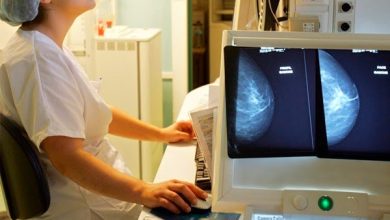

Enfermera del Hospital de Arica obtiene el primer lugar nacional en proceso de capacitación oncológica